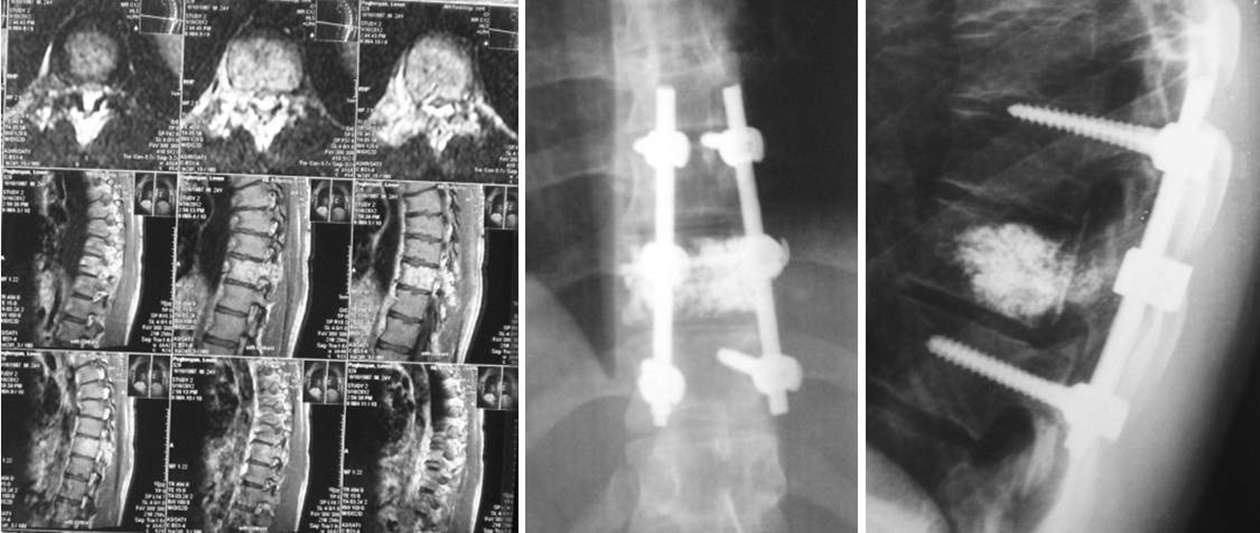

Dr. Momjyan significantly contributed in the development of spinal surgery in Armenia. He uses modern technologies and carries out the treatment of various spine diseases and injuries, such as:

• degenerative diseases of spine (low back pain, herniated discs, stenosis of spinal channel, instability of the vertebrae)

• spondylolysis or spondylolisthesis of the lumbar part of the vertebrae

• malignant and benign tumors of the spine

• fractures and dislocations of the vertebrae

• correction of post-traumatic and postoperative spinal deformities